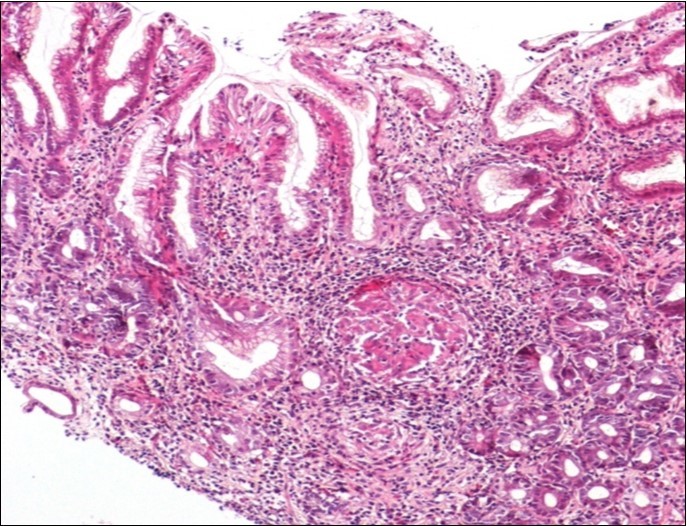

Concerning the etiology, diagnosis was made regarding to the past medical facts, the clinical symptoms, the endoscopic findings and the histological associated lesions. The main etiology was represented by Crohn’s disease in ten cases, followed by gastric tuberculosis in 6 cases. H Pylori was the retained cause of gastric granulomatosis in 5 cases, regarding to the absence of other etiologies, and the favorable issue after antibiotic eradication treatment. In 5 other patients, etiology of gastric granulomatosis was also found and the final diagnosis was a sarcoidosis (n=3), foreign body reaction (n=1), and yersiniosis (n=1). In our series, thirteen cases were unclassifiable despite etiological investigations and no cause of gastric granulomatosis was isolated. Histological findings of a case of tuberculosis and sarcoidosis are represented in Figure 1 and Figure 2.

Figure 1.Histological aspect of gastric granulomatosis secondary to tuberculosis : Antral biopsy specimens revealing multiple necrotizing (caseating) granulomas ( HEx100)

Histological aspect of gastric granulomatosis secondary to             tuberculosis : Antral biopsy specimens revealing multiple necrotizing (caseating) granulomas ( HEx100)